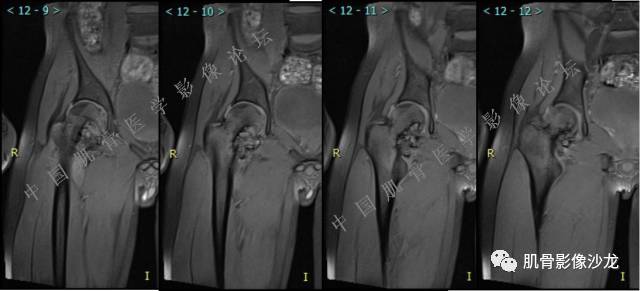

主诉:右髋及右膝部疼痛3月余

现病史:3月前打球时自觉右大腿肌肉拉伤后右髋及右膝部疼痛,自服“活血化瘀”类药物(具体不详)后自觉疼痛缓解,2月前打球时再次扭伤,右髋及右膝部疼痛明显,行走时疼痛加重,自服药物治疗,效果不佳,遂来诊。

张小林 20:13 磁共振有双低信号,结合CT确实要考虑有纤维成份。

医影在线 20:13 干骺端溶骨性破坏,边缘模糊,低密度肿块,似有钙化

Echo 20:13 有骨质破坏,边界不清,有软组织肿块,我觉得恶性是要考虑的

Echo 20:16 软组织肿块突破了骨皮质

Echo 20:23 我个人觉得,17岁男性,病灶发生在原干骺端区域,溶骨性骨质破坏,似有肿瘤骨,有软组织肿块形成,从常见病发生率来说,骨肉瘤还是要考虑的